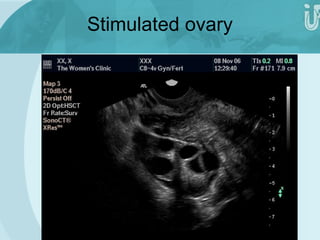

Stimulated ovary